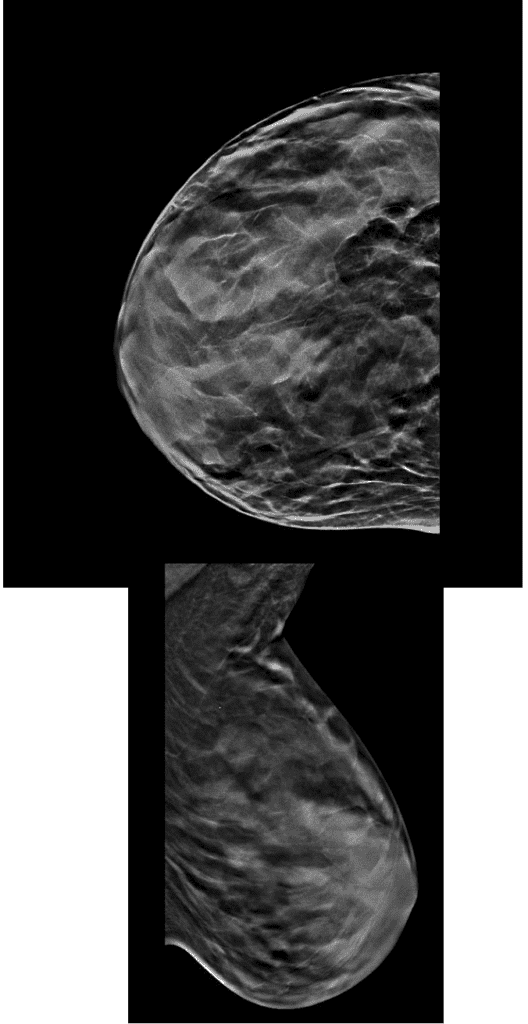

These mammogram images demonstrate the dense gland present in a patient with hypolactation and normal anatomic appearance of her breast. She had a history of growth hormone deficiency in childhood that likely impacted the cellular differentiation of her lactocytes during puberty.